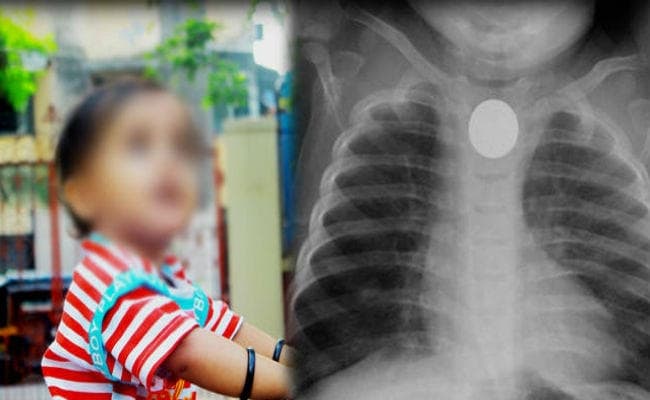

दोपहर तीन बजे के करीब एक परिवार सात साल के बच्चा के साथ पहुंचा. बच्चे के गले में पांच रुपये का सिक्का अटक गया था. जूनियर डॉक्टरों की हड़ताल के कारण पीड़ित बच्चा मइबुल लस्कर और उसके परिवारवालों को काफी परेशान होना पड़ा. पहले तो उस परिवार को गेट पर ही रोक दिया गया. इस दौरान बच्चे के इलाज के लिए परिवार बिलखता रहा. करीब दो घंटे बाद एक्सरे रिपोर्ट दिखाने पर उस परिवार को अंदर जाने दिया गया.

जानकारी के अनुसार जीवनतल्ला निवासी मइबुल अपने घर में गुरुवार को सुबह दस बजे खेल रहा था. परिवारवालों का कहना है कि बच्चा खेलते-खेलते ही अपने मुंह में एक पांच रुपये का सिक्का डाल लिया. वह सिक्का उसके गले में अटक गया. इसके बाद से बच्चा उल्टी करते-करते परेशान हो गया.

घटना के बाद परेशान घरवाले इलाज के लिए दौड़ भाग करने लगे थे. स्थानीय एक चिकित्सा केंद्र से एक्सरे करवाने पर पता चला कि सिक्का बच्चे के गले में फंसा है. फिर बच्चे की दादी बी. लस्कर, चाचा और मामा तुरंत उसे लेकर सीएनएमसीएच पहुंचे. वहां काफी देर तक गेट पर ही रोक कर रखा गया. फिर अंत में दो घंटे बाद उसे भर्ती लिया गया. सात घंटे तक परिवारवालों को परेशानी झेलनी पड़ी. रात आठ बजे बच्चे के गले से सिक्का निकाल दिया गया.